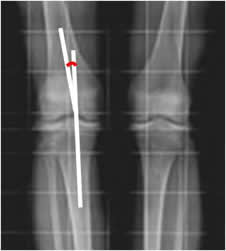

Fig 66. Angulo femorotibial.

Rx AP. Medición del ángulo entre los ejes del fémur y la tibia.

Fig 67. Angulo femorotibial.

Rx AP. Medición del ángulo entre los ejes del fémur y la tibia, el cual tiene normalmente vértice medial.

El niño desde el nacimiento hasta los 24 y 30 meses, puede presentar un genu varo fisiológico. (Fig 68). Este debe ser bilateral y con una distancia menor de 6 cm, entre los cóndilos femorales. El ángulo del eje femorotibial no debe ser mayor de 28º y no requiere de tratamiento. Si el genu varo persiste después de los 36 meses, se debe diferenciar del raquitismo, la enfermedad de Blount (Retardo en el crecimiento posteromedial de la tibia, la cual es mas corta), malformación congénita, infección, trauma, osteoartrosis, etc. (1). (Fig 69 y 70).

Se considera patológico un ángulo femorotibial mayor de 177º y cualquier genu varo unilateral. (1).